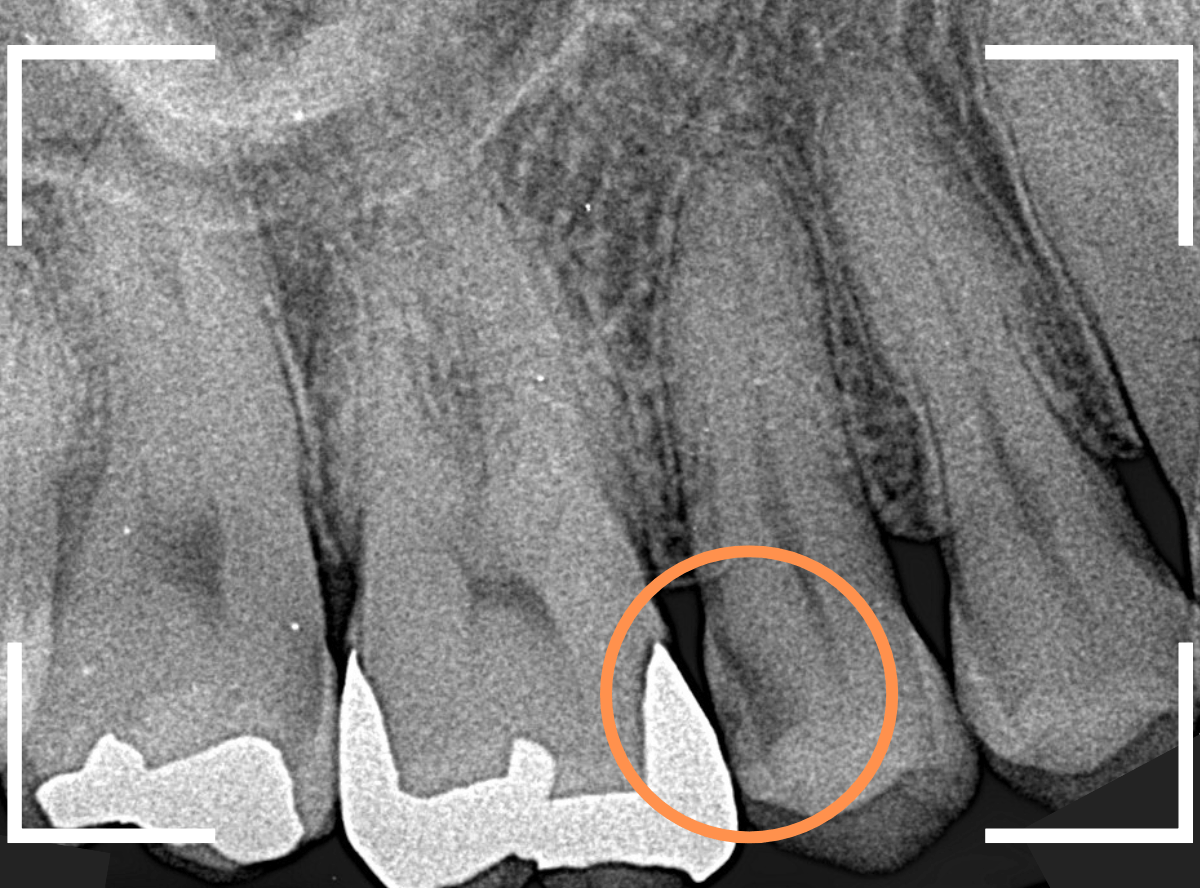

Case.22 痛みはないけど、歯のすきまから大きな虫歯

上の小臼歯の間が虫歯になっていた患者さんです。

症状はありませんし、見た目からも虫歯があるかはわかりませんでした。

レントゲン写真で確認します。

赤い線が虫歯、青い線が歯の神経です。

歯のすきまから両側に虫歯が大きく広がっているのが確認できます。

レントゲン写真からある程度確認出来ましたが、歯の神経スレスレまで虫歯が進行していました。